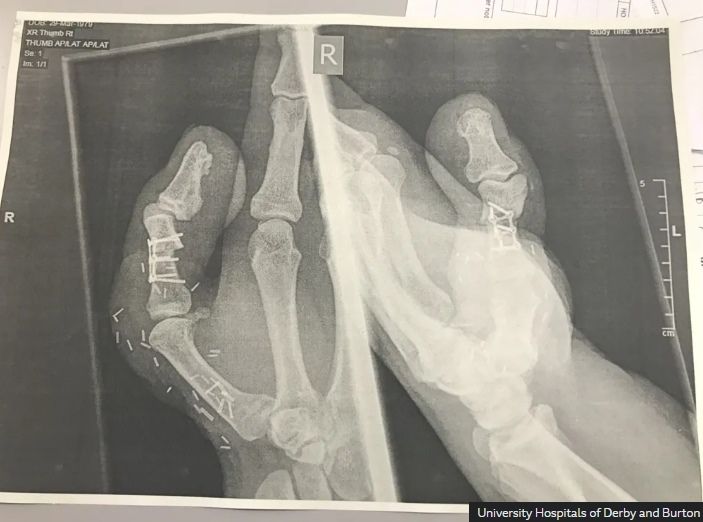

사고 직후 그는 인근 병원으로 옮겨졌고, 의료진은 여러 재건 수술 방법을 고심한 끝에 리의 오른발 엄지발가락을 절단해 잘려 나간 엄지에 붙이는 이식 수술을 진행했다.

발과 손을 동시에 수술하는 수술은 총 10시간가량 소요됐다. 수술은 성공적으로 끝났지만 회복 과정은 쉽지 않았다.